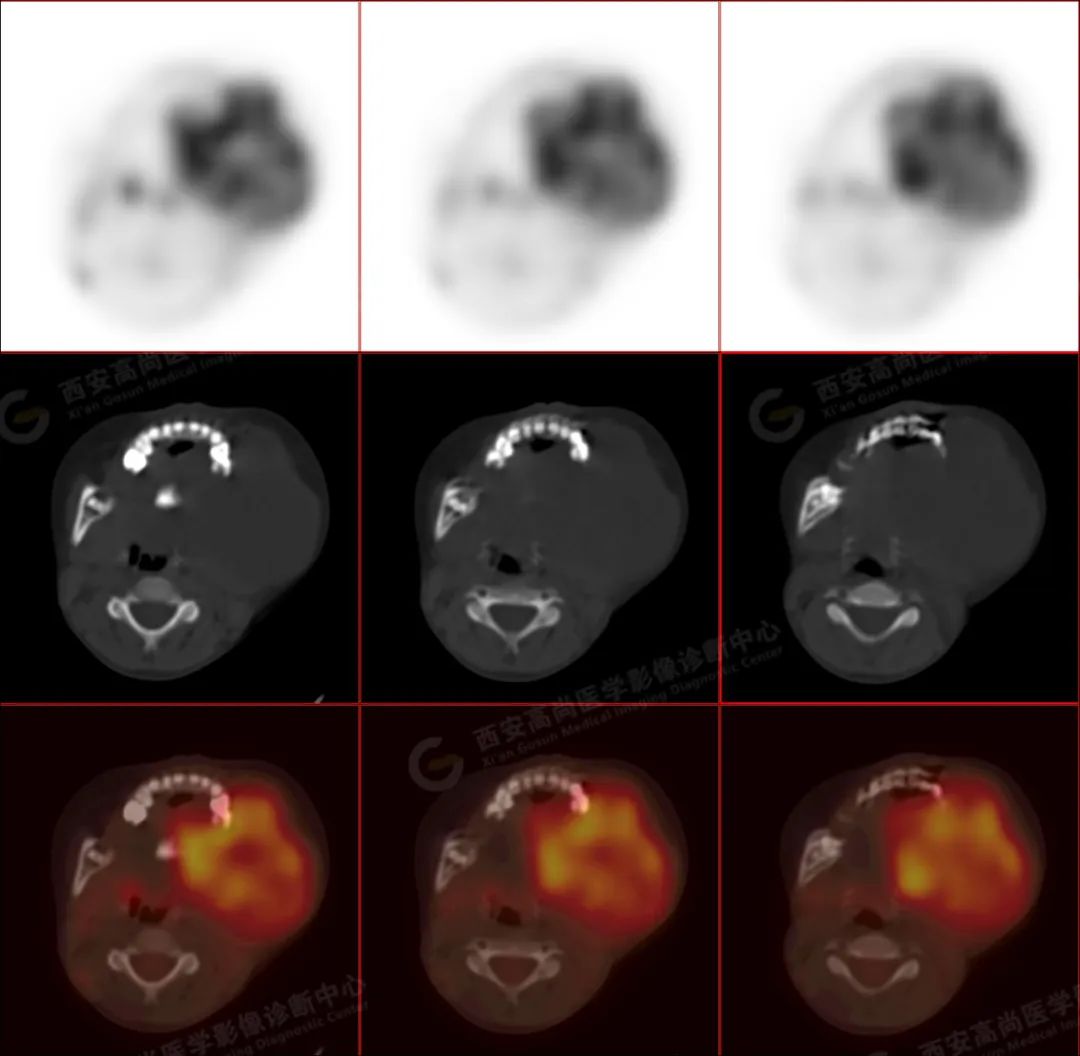

左侧下颌区可见巨大团块状软组织肿块,大小约 6.6 cm×5.8 cm×6.1 cm,向上达左侧颞下窝上缘,向下达下颌前联合,相邻左侧咬肌、颊肌等肌肉组织分界不清楚,左侧口底、咽部、腮腺受压改变,肿瘤包绕及侵犯左侧上颌升支、蝶骨翼突外板,呈 FDG 代谢不均匀异常增高,考虑为恶性病变,横纹肌肉瘤可能性大。

3.PET/CT 能够提供肿瘤代谢信息,并且提供肿瘤分期。分化程度越差的病灶 FDG 代谢明显增高。